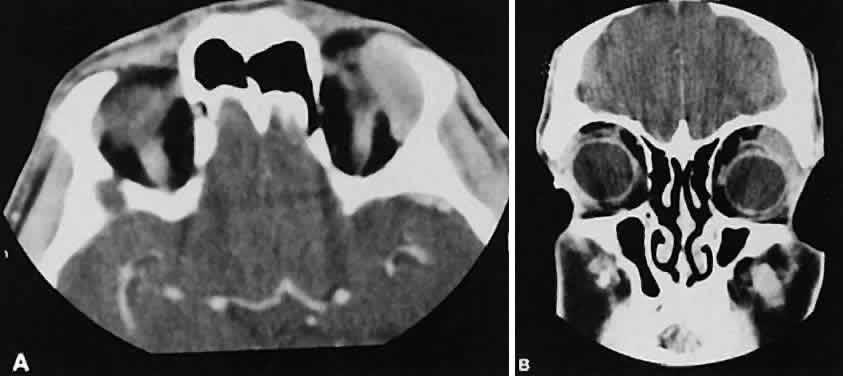

| Abnormal size of the optic nerve and sheath on the CT scan usually is pathologic. Rothfus

and colleagues49 suggested a differential approach based on high-resolution CT morphology. An enlarged optic nerve also is associated with an age-related differential diagnosis. Most gliomas are found in children, whereas optic nerve sheath meningiomas tend to afflict adults, primarily women. Nevertheless, there are exceptions for each. Optic nerve gliomas are associated with neurofibromatosis. A prospective study determined that a child with known neurofibromatosis has a 15% chance of having a glioma of the anterior visual pathway. Conversely, a child with an optic nerve glioma has a 25% chance of having neurofibromatosis.50 Although an optic nerve meningioma can occur in association with neurofibromatosis, particu-larly NF-2,51 the association is not as firmly established as with gliomas. It is uncommon but well-established that optic nerve meningiomas can occur during childhood. Not only can they create confusion regarding differentiation from optic nerve glioma, but, most important, they behave in a more aggressive fashion.52 The CT evaluation of optic nerve lesions is facilitated by the use of 1.5-mm axial slices and intravenous contrast.49 Gliomas usually appear as a fusiform enlargement with sharp delineation from the surrounding tissue due to circumscription by an intact dura (Fig. 10). Kinking and buckling of the optic nerve along with infarctive cysts are typical findings in an optic nerve glioma. Bilaterality and intracranial involvement of the anterior visual pathway also may be noted. The radiographic signature of an optic nerve meningioma is more variable (Fig. 11). The optic nerve shadow tends to be diffusely enlarged, with irregular expansion along the optic nerve. Jakobiec and colleagues53 found diffuse enlargement of the optic nerve with apical expansion to be the most frequent pattern. Calcification within the optic nerve shadow, which is unusual in optic nerve gliomas, is common with optic nerve meningioma. The irregular excrescent margins most likely signify extradural invasion into the adjacent orbital soft tissues. A central linear lucency extending the length of the optic nerve shadow also is a typical finding of an optic nerve meningioma.49 These two lesions represent the most frequent tumors affecting the optic nerve. Other reported tumors include hemangioblastoma, leukemic infiltration, and involvement by metastatic disease. Enlargement of the dural sheath around the optic nerve, an optic nerve meningocele, can be confused with a tumor.54 The radiographic procedure of choice for evaluating suspected optic nerve lesions is MRI with gadolinium and high-resolution, fat-suppression techniques. ORBITAL TUMORS In a patient with an orbital mass, CT can show not only the mass but also other valuable information such as shape, location, consistency, intralesional calcium, and effect on surrounding structures.55 Contrast enhancement offers some ideas about vascularity. VASCULAR TUMORS The vascular tumors under consideration are capillary hemangioma, cavernous hemangioma, lymphangioma, and hemangiopericytoma. Capillary hem-angiomas and lymphangiomas are benign infiltrativetumors seen in a pediatric population. Capillary hemangiomas have a homogeneous consistency, display intense uniform contrast enhancement, and do not usually displace any orbital structures (Fig. 12). Phleboliths are a characteristic finding in hemangiomas and, when present, are virtually pathognomonic of this diagnosis.56 Lymphangiomas have a cystic component, which, on occasion, may hemorrhage into itself, accounting for rapid onset of symptoms and clinical/radiographic evidence of mass effect (Fig. 13). In all likelihood, scans require sedation for an adequate study. Thin (1.5-mm) axial views with computer reformatting for coronal views along with contrast enhancement should provide an adequate study.

Both cavernous hemangiomas (Fig. 14) and hemangiopericytomas typically are seen in adults. Their radiographic appearance is similar and shows a well-demarcated, contrast-enhancing mass, although more intense enhancement may be seen with the hemangiopericytoma. The differential diagnosis of a well-demarcated, contrast-enhancing lesion is listed in Table 3.